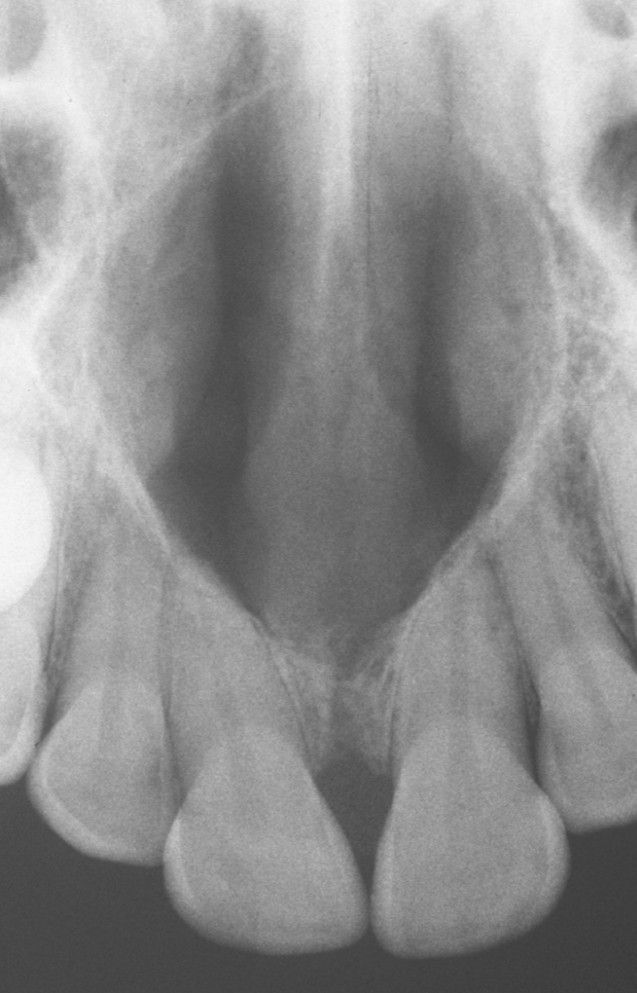

Nasopalatine duct cyst

Large destructive cyst of the palate.